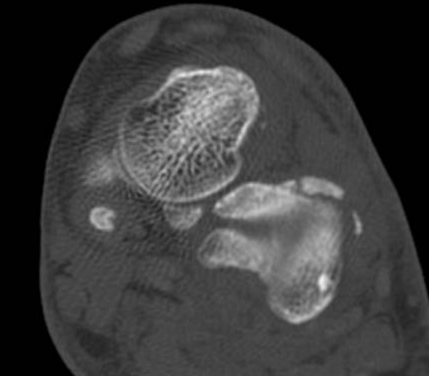

ÄÄÇ»ÅÍ ÃÔ¿µ : Á¾°ñÀÇ °ñÀý , µÎ ºÎÀ§(÷ºÎ ÆÄÀÏ Âü°í)

ÄÄÇ»ÅÍ ÃÔ¿µ ÆÇµ¶¿¡¼­ Á¾°ñÀÇ µÎ ºÎÀ§ °ß¿­°ñÀýÀÌ ¾ð±ÞµÇ¾úÁö¸¸ ÃÊÀ½ÆÄ°Ë»ç»ó  Ãß°¡ÀûÀÎ °ñÀýÀ»

È®ÀÎÇÒ ¼ö ÀÖ¾ú´Ù.

ÄÄÇ»ÅÍ ÃÔ¿­»óÀÇ °ñÀý ºÎÀ§´Â ÃÊÀ½ÆÄ°Ë»ç¿¡¼­ È®ÀÎÇÒ ¼ö ÀÖ¾ú°í »çÁø 10~15¿¡¼­ È®ÀÎÀÌ °¡´ÉÇÏ´Ù.